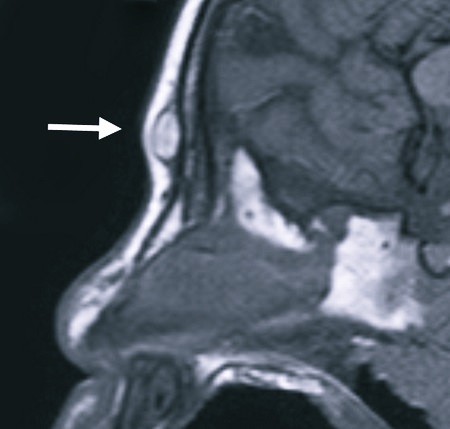

- Пинеальная. Эта редкая разновидность поражает эпифиз.

Еще один вид – киста, расположенная в сосудистых сплетениях. Ее часто диагностируют еще в утробе матери, на ранних этапах развития плода. В мозге есть сплетения сосудов, которые вырабатывают спинномозговую жидкость. Именно они и могут часто поражаться, становясь областью расположения кисты. При таком новообразовании функции мозга не нарушаются, он нормально развивается. Кисту сосудистых сплетений часто диагностируют у новорожденных. Часто она самостоятельно проходит, не требуя никакого лечения, но все равно нужно получить консультацию детского невропатолога.